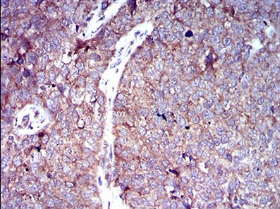

IHC    1/200 - 1/1000